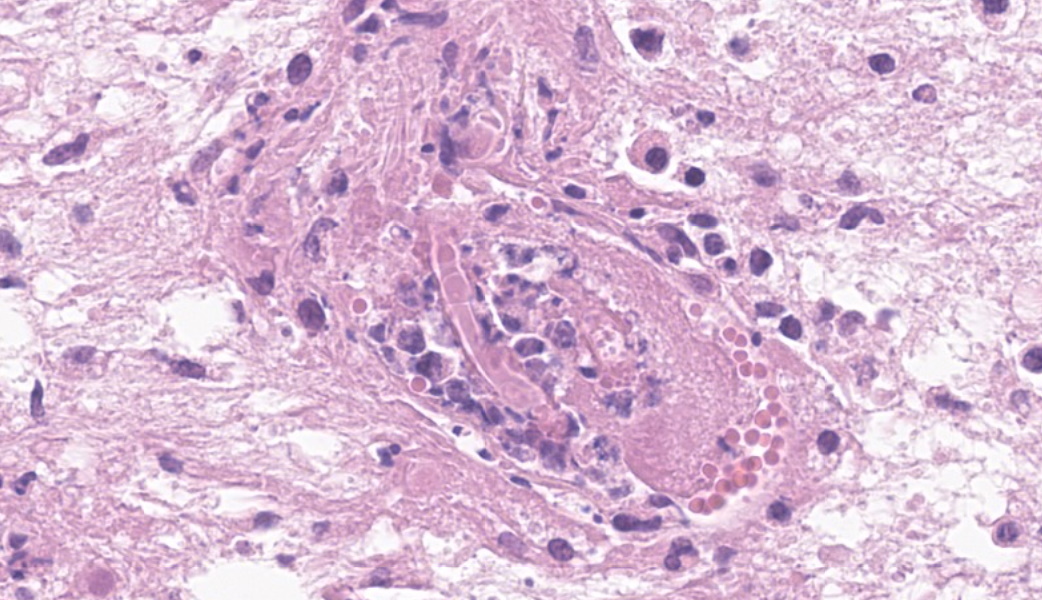

Brain, right frontal lobe: the leptomeninges are focally extensive and moderately expanded by pyogranulomatous exudate. The exudate is formed by nodular to coalescent (mild slide variation) collections of epithelioid macrophages, lesser eosinophils, lymphocytes and plasma cells and few Langhans giant cells. The granulomatous component is admixed with plump fibroblasts, thin bundles of fibrous tissue, and multifocal aggregates of granular, deep basophilic and dense material (mineral). Among the cell debris or in the cytoplasm of the multinucleated cells there are tubularly elongated (when longitudinally sectioned), circular or oval (when transversally sectioned) structures barely stained and hard to visualize in hematoxylin and eosin (HE) stained slide ("negative" images of fungal hyphae). The hyphae are characterized by a body that is hollow or filled with eosinophilic or basophilic granular material and surrounded by varying, but mostly scarce, amounts of strongly eosinophilic, smooth or granular material (Splendore-Hoeppli reaction). The wall of medium-sized arteries in the affected areas is segmentally or cincunferentially expanded by acellular, bright eosinophilic and homogeneous material (fibrinoid necrosis) and occasionally there are hyphae infiltrating the vessel wall or associated with thrombosis in the vessel lumen. There is a focally extensive area of necrosis of liquefaction, swelling of astrocytes and cavitation of nervous tissue, where the parenchyma has been replaced by proliferating microglial cells, many of which already differentiate into foamy macrophages (gitter cells). Perivascular cuffs containing up to three layers of lymphocytes are also observed. The organisms stain well by the GMS method as slightly branched hyphae with an irregular diameter of 7-10 μm, associated with foci of necrosis. Occasionally there is a rounded structure of larger diameter (up to approximately 15 μm) at the end of the hyphae.Lung: there are focal to coalescent areas of consolidation consisting of nodules or sheets of large numbers of epithelioid macrophages and Langhans giant cells admixed with numerous eosinophils and surrounded by fibroblasts and fibrous tissue. The macrophages encircle hyphae similar to that described in the brain that are surrounded by moderate to abundant Splendore-Hoeppli material. Throughout the lung parenchyma there are also small multifocal areas of necrosis containing hyphae. Mineralization is sparsely observed amid necrosis and inflammation. Diffusely, the reminiscent alveolar septa are mildly infiltrated by neutrophils and eosinophils.

Brain, pyogranulomatous meningoencephalitis, focally extensive, with fibrinoid vasculitis and trombi, associated with intralesional fungal hyphae, morphology consistent with Conidiobolus sp.Lung, pyogranulomatous pneumonia, multifocal to coalescent, associated with intralesional fungal hyphae, morphology consistent with Conidiobolus sp.

- Cerebrum: Meningoencephalitis, pyogranulomatous and necrotizing, chronic, focally extensive, severe, with vasculitis, thrombosis, and numerous intravascular and intrahistiocytic fungal hyphae.

Discussion focused on indicative features of a zygomycete histologically, which include a broad diameter ranging from 5-15um, non-parallel thin walls, rare septations, asymmetric acute-angle branching, and potentially a terminal bulb. Zygomycetes are typically weakly PAS-positive and more strongly GMS-positive. This correlated nicely with the PAS and GMS stains run in-house. Other differentials mirrored those discussed by the contributor, including oomycetes like Pythium insidiosum, which would be PAS-negative and GMS-positive, as well as Basidiobolus spp., another member of the Entomophthoramycota family alongside Conidiobolus. However, Basidiobolus spp. typically affect the thorax, trunk, limbs, intestinal tract, and, in atypical cases, can cause systemic infection.28Conidiobolus is far more commonly seen localized to face and nostrils. Using a variety of proteases (including elastase and collagenase), lipases, esterases, and glycoside hydrolases at their disposal, Conidiobolus spp. can wreak havoc to the nasal and facial bones and surrounding soft tissues24. Ultimately, they may eat through the cribriform plate and enter the brain.28,29 It’s pretty much “game over” at that point.